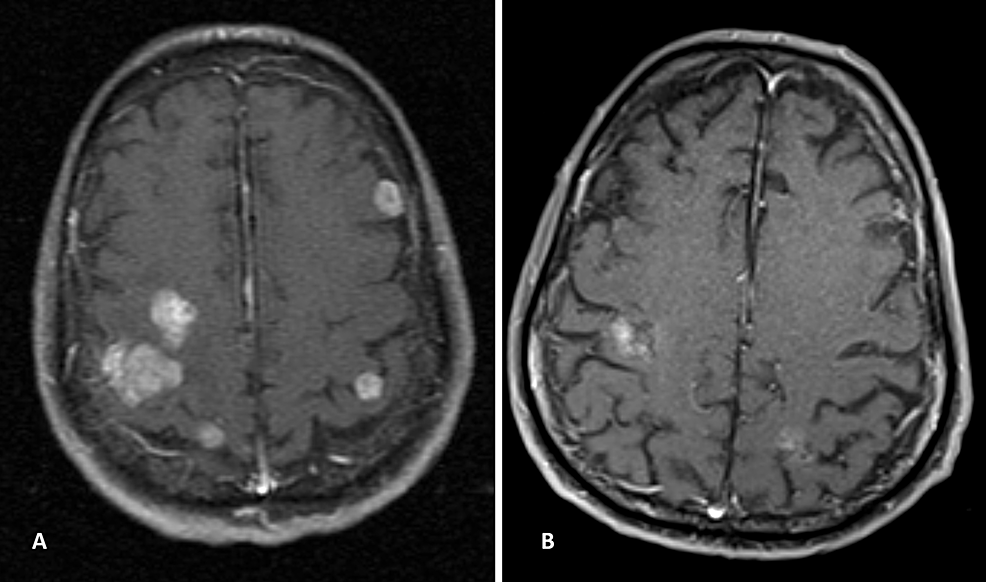

Brain mass lesions in HIVinfected patients by enhancedMRI

(PDF) MRI imaging features of HIVrelated central nervous system Hiv Brain Cancer Do people infected with human immunodeficiency virus (hiv) have an increased risk of cancer? Why might people infected with hiv have a higher. Persons with hiv infection have chronic antigenic stimulation, inflammation, and cytokine dysregulation (even with hiv control. Learn about the neurological disorders caused by hiv, including aids dementia complex (adc), a severe form of cognitive. Hiv Brain Cancer.